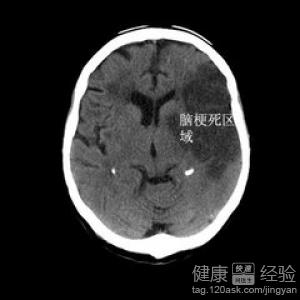

老人腦梗塞吃什麼好水果可以帶你調養腦梗塞

腦哽塞是中老年人群中常患的一種疾病。很多人都會患有腦梗塞這種疾病,在患者承受巨大的痛苦,費盡千辛萬苦治療康復後,不久就會又復發。這種疾病復發的概率非常大。所以腦梗塞,患者的調養,治療都很重要。有很多水果對於腦梗塞患者有極好的治療作用,他們能夠幫助腦梗塞患者減輕病症,及早康復。所以腦梗塞的患者應該多多注意這類的食物。